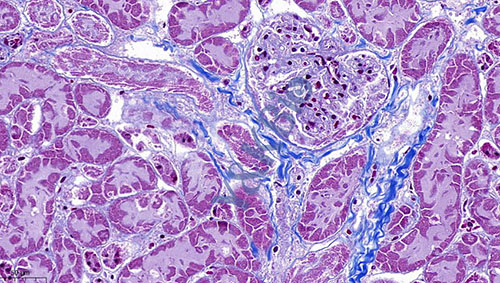

陕西Masson染色是病理染色服务中比较常见的一种,Masson染色用于胶原纤维和肌纤维的染色及鉴定;染色结果:胶原纤维呈蓝色、肌纤维呈红色、细胞核呈蓝黑色。